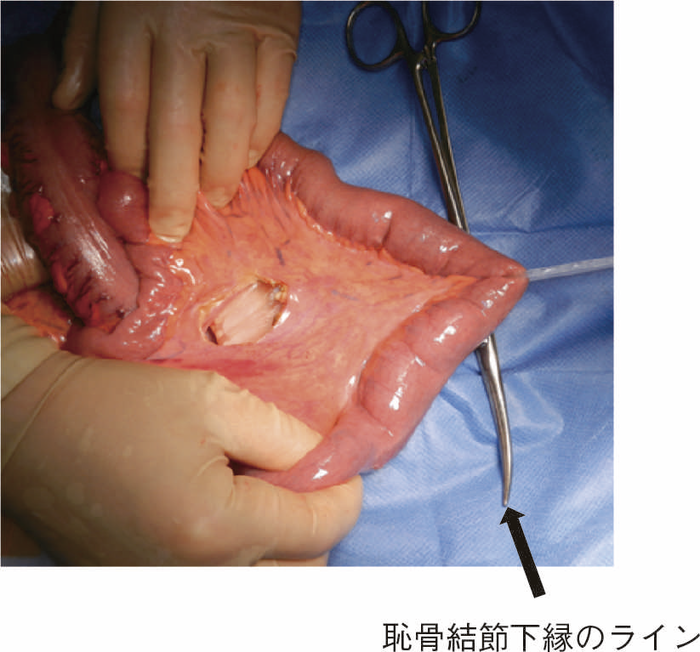

直腸粘膜をすべて切除し,回腸囊と肛門を手縫い吻合する。UCに対しても根治性が高い術式である。図14のように,肛門管粘膜の切除開始ラインは歯状線の肛門側で,肛門陰窩をすべて切除する。切除開始ラインが歯状線よりも口側になり,一部肛門管粘膜(移行帯上皮)を温存させた結果,この残存した粘膜からの発癌を強く示唆する症例報告も存在する2)。また,IAAを行ったにもかかわらず,術後に発癌したという症例報告も存在するが,多くは術後3年以内に発症している症例が多く,術前の直腸癌の局所再発が原因ではないかとの意見が一般的である3)。下部直腸から肛門管にかけて早期癌を合併するような症例では,術後の病理検査で,DM0,RM0であっても図15のように局所再発を生じる可能性もあるので,定期的な画像診断とともに,直腸診を行い,局所再発がないことを確認すべきである4)。

CQ 16で述べたように,UC関連大腸腫瘍を合併した症例に対してはIAAが推奨されるが,技術的にIAAが実施可能な体型かという問題も考慮しなければならない。図16のように回腸間膜を開窓してpouch topの位置確認を行うが,恥骨結節の下縁よりも少なくとも2 cm程度肛門側まで進展しない場合は,肛門吻合は難しい。術中判断で回腸囊が肛門まで到達することが困難な症例では回腸囊肛門管吻合術(ileoanal canal anastomosis:IACA)+術後のATZ(anal transitional zone)の内視鏡的サーベイランスという選択肢も考慮する必要がある。ただ,下部直腸に腫瘍が存在する場合はこの選択はできない症例もあり,大腸全摘,永久回腸人工肛門造設術が必要になることもあるので,術前に十分にインフォームドコンセントを得ておく必要がある。(2)大腸全摘,回腸囊肛門管吻合術(ileoanal canal anastomosis:IACA)

図16 回腸間膜の開窓とPouch topの位置確認